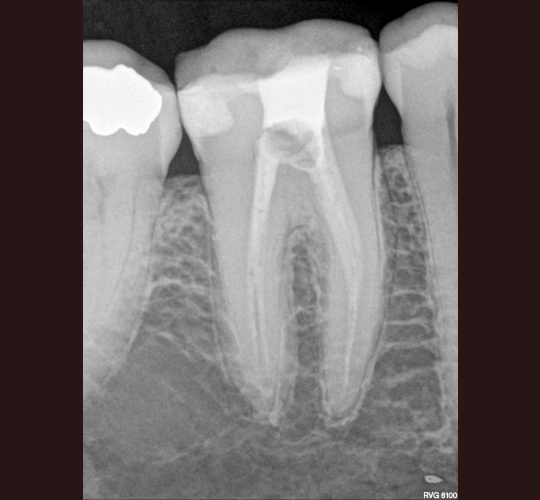

Endodontic Treatment: Case #10 – 4 canalled lower first molar with 2 distals and 2 mesial canals with a common apex of the mesial root system. By | April 2, 2024 MB and ML join at the apex with inter connections of the two root systems (anastamosis). pre-op medicated with CaOH final final x-ray mesial angled showing interesting anatomy Posted in Endodontics